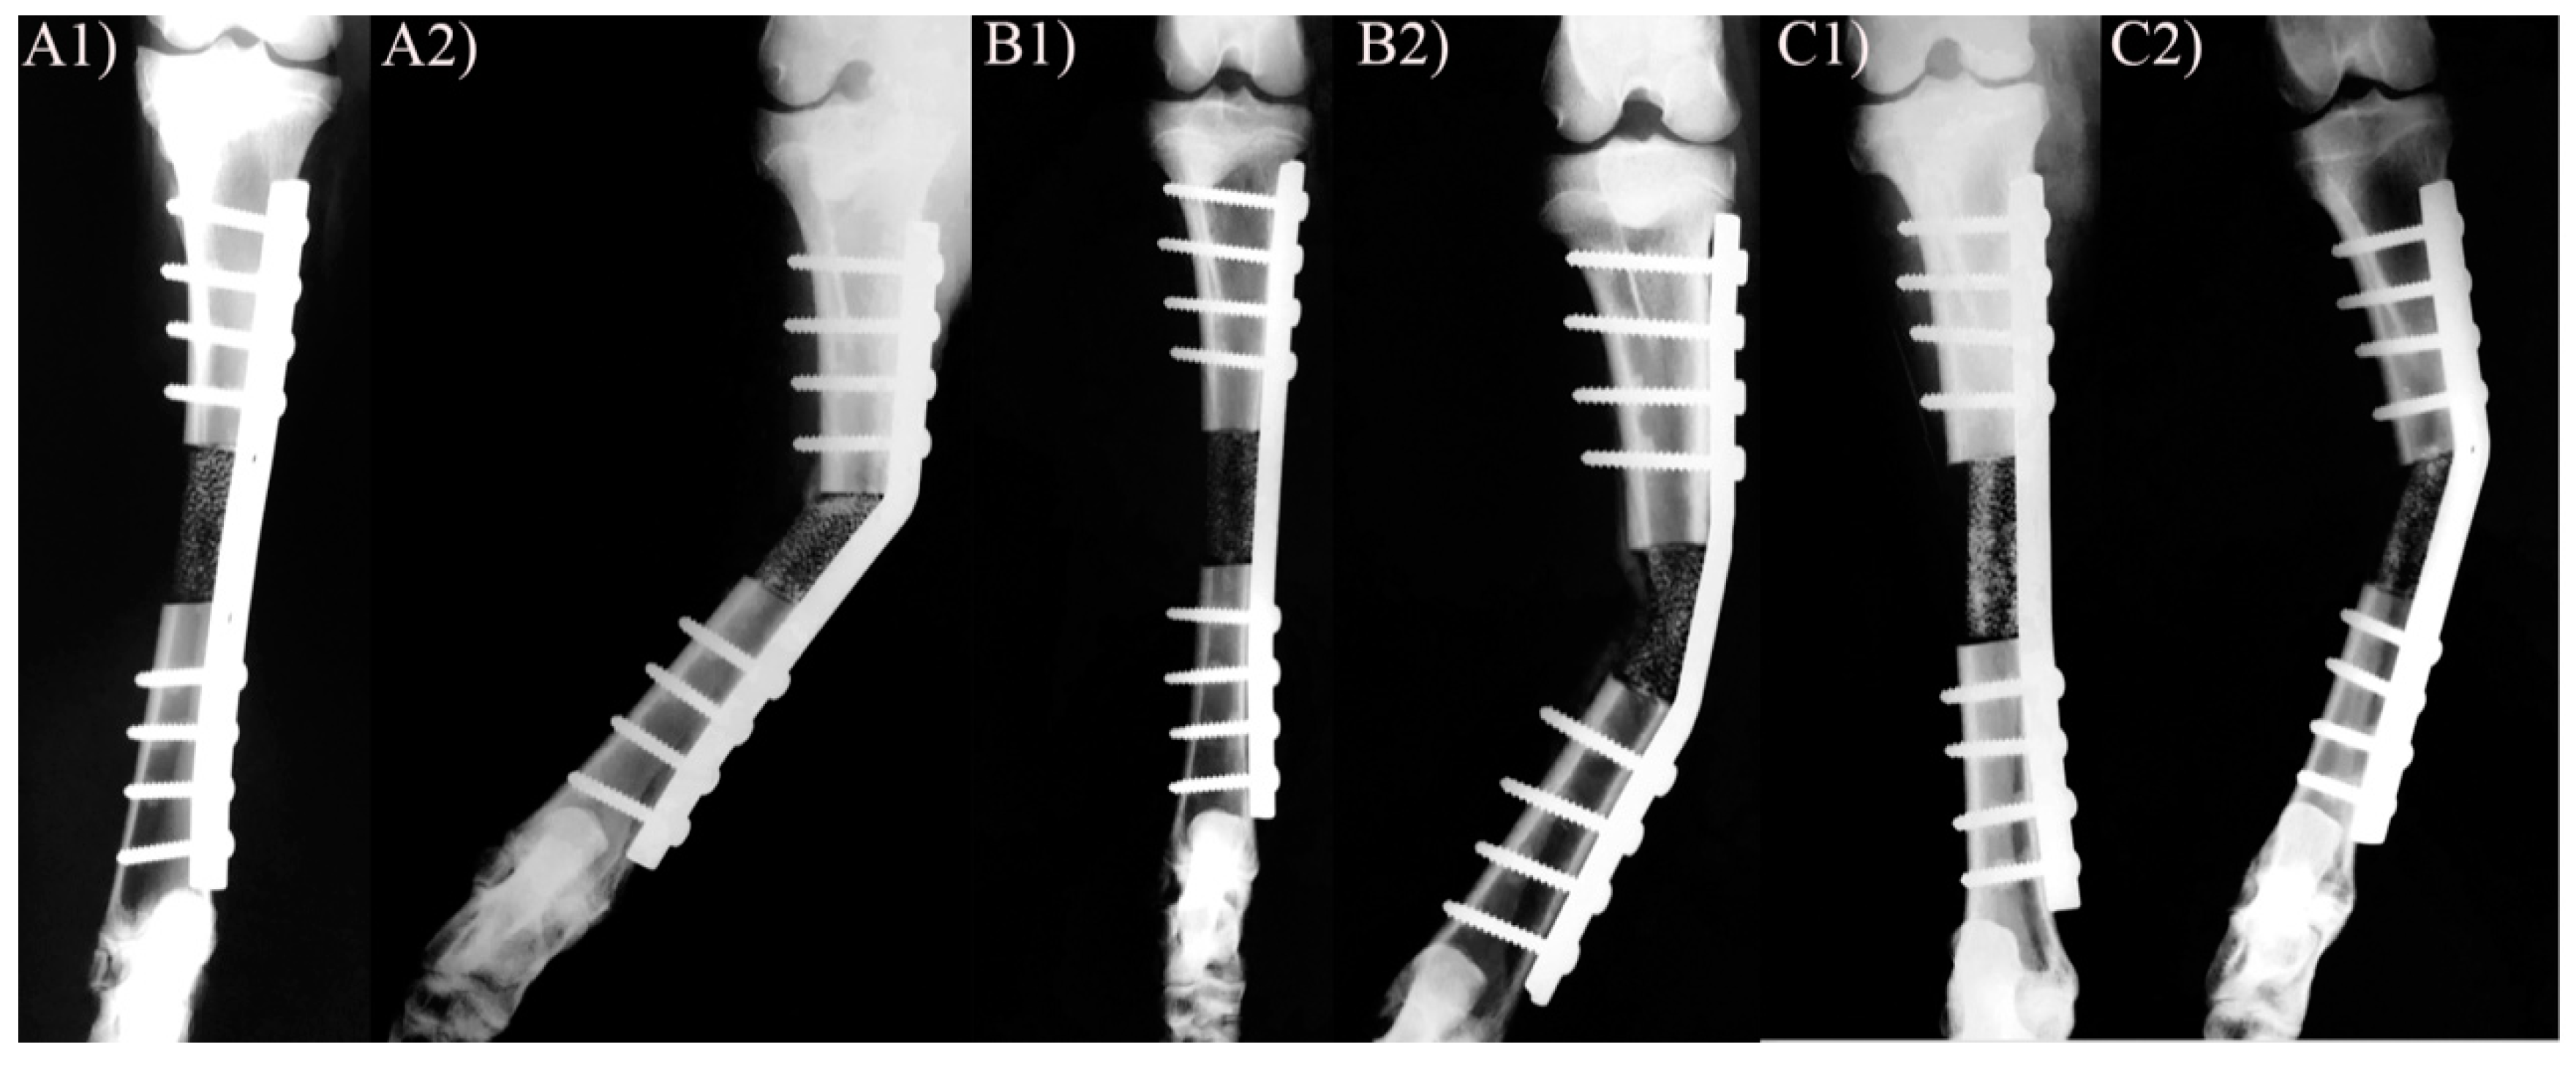

3.1. X-ray and Clinical Follow-Up